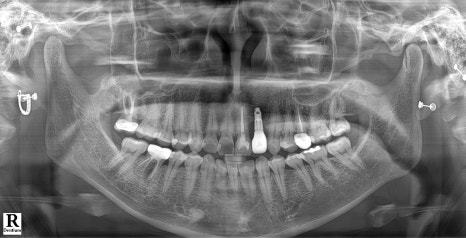

Left photo: “This is the X-ray taken at the patient’s first visit. The tooth in the middle of the front teeth (#22) had an implant placed, and the others were all natural teeth.”